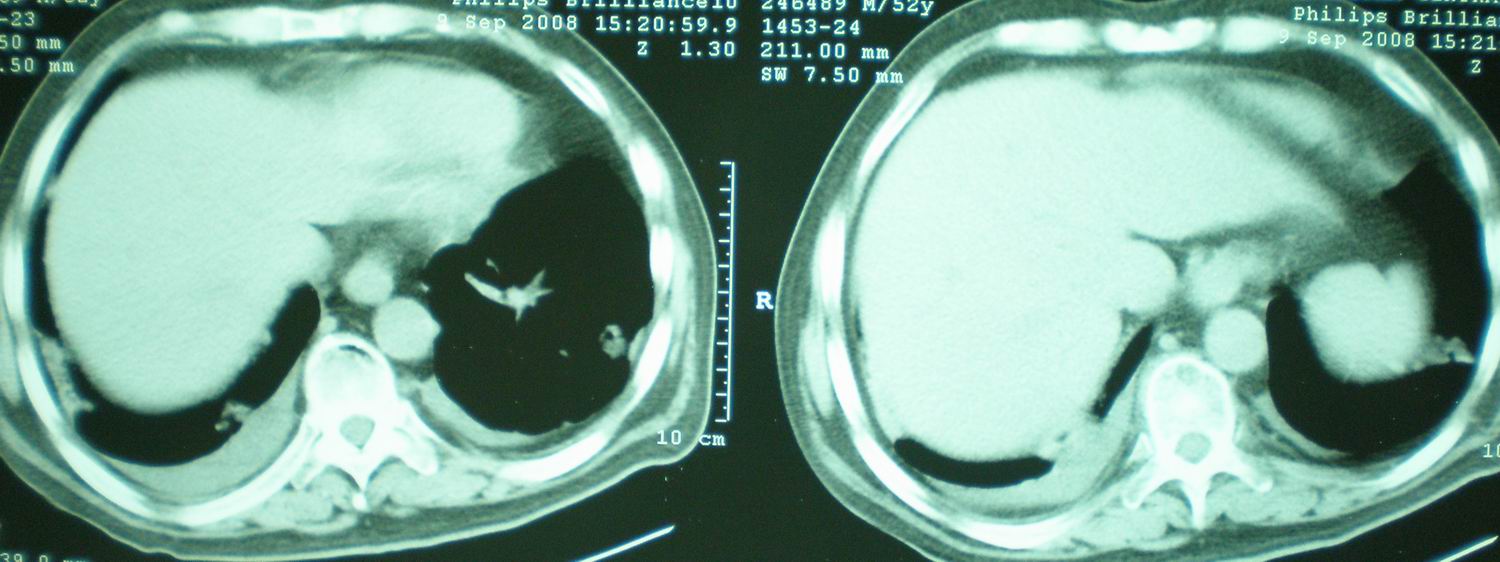

病人资料:男,52岁,因体癣股癣等皮肤病行激素治疗,因突然大剂量减药而起病,病情危急,9月8日曾在上级医院住院治疗,9月18日复查了ct片,相关检查及住院小结以图片资料上传。

2008年11月18日今天的ct片

2008年9月18日ct片

2008年9月8日ct片:

[face=宋体]显然上级医院进行了抗结核,抗真菌,抗炎等治疗,目前病人肺内病灶基本消失,双侧胸腔积液,右侧积液量有吸收,抗结核一个多月,现在病人疑问,结核的诊断是否有疑义,抗结核是否继续,因为那个毕竟副作用大。[/face]

我仔细看了下病人的出院小结,当时情况危急,诊断里有1型呼衰。心包周围的是脂肪密度。结合三次ct扫描的图象分析,个人认为:1、病人目前肺部病灶基本消失,双侧胸腔内少量积液,抗结核治疗才一个多月,就算是结核,抗结核治疗有效果,为何效果如此好,一点纤维灶的痕迹都没有呢,再就是患者做过气管镜检查及活检、痰检均未找到结核的证据。所以不支持结核的诊断。

2、结合现在的ct片,考虑:肺水肿及真菌感染,双侧胸腔积液。